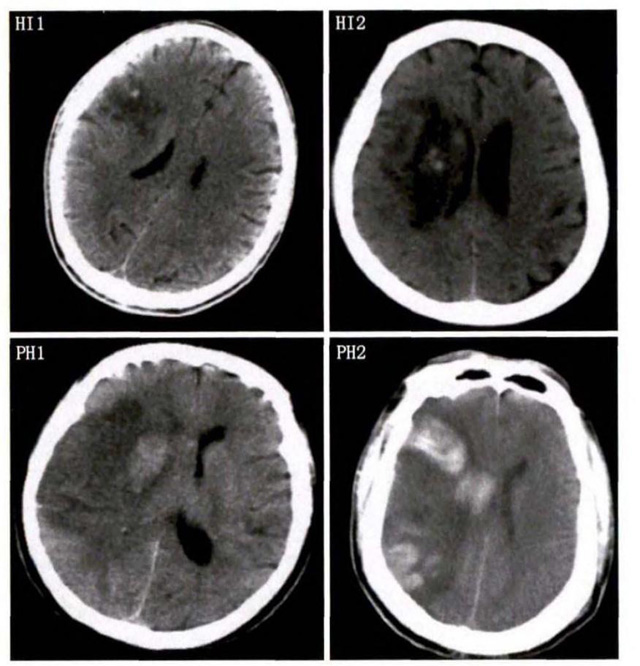

中、老年病患,有動脈粥樣硬化及高血壓病等腦卒中的危險因素,發(fā)病結(jié)合神經(jīng)系統(tǒng)癥狀和體征,應當考慮急性腦梗死的可能。再經(jīng)腦CT/MRI發(fā)現(xiàn)梗死灶,或排除腦出血、炎癥性疾病等,診斷即可確定。腦梗死有時頗似小量腦出血的臨床表現(xiàn)。腦栓塞在任何年齡都可以有發(fā)病的風險,可以在幾秒到幾分鐘達到頂峰。會有偏癱不能說話等局部神經(jīng)功能損壞。栓子來源很種,可能是冠心病、心肌梗塞、心內(nèi)膜炎等。合并心房纖顫,結(jié)合其他臟器官的支持診斷,CT跟磁共振都可以檢查確定栓塞位置數(shù)量還有是不是有伴發(fā)出血等問題??梢詭椭\斷。

中老年有高血壓糖尿病發(fā)病病史,起病神經(jīng)功能缺損癥狀,臨床表現(xiàn)為腔隙綜合征,即可初步診斷本病。如果CT或磁共振證實有與神經(jīng)功能缺失一致的腦部腔隙病灶, 符合大腦半球或腦干深部的小穿通動脈病變,即可明確診斷。少數(shù)患者隱匿起病,無明顯臨床癥狀,在影像學檢查時發(fā)現(xiàn)。